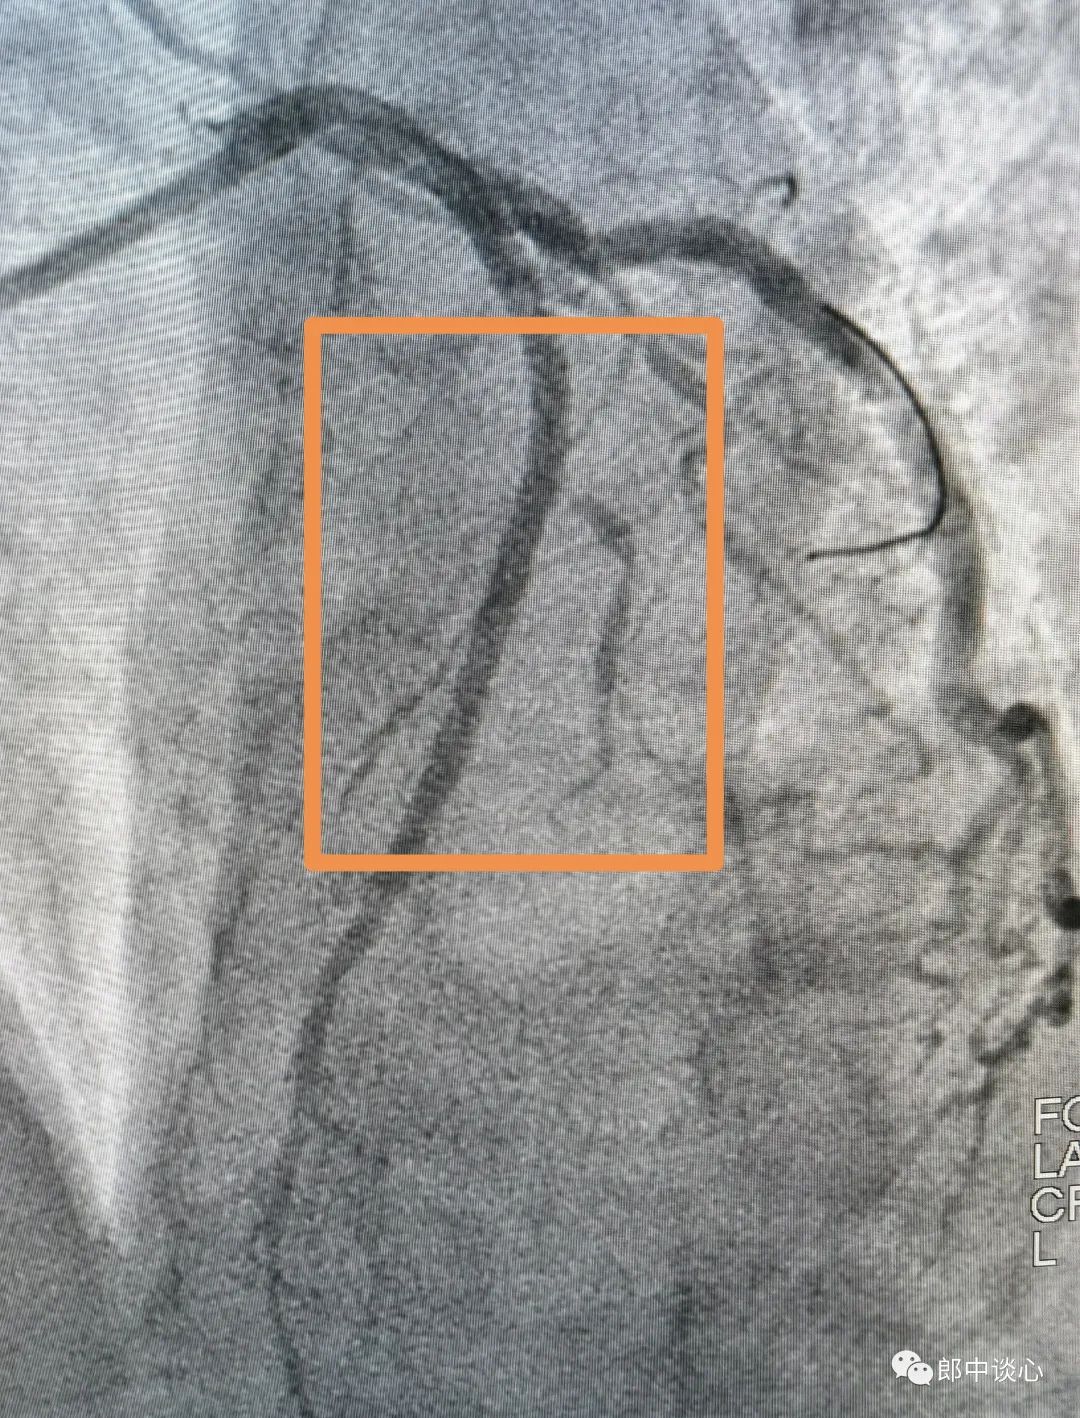

冠脉造影,果然前降支完全闭塞了!回旋支也是重度狭窄且是不稳定病变!(黄框内为病变段)